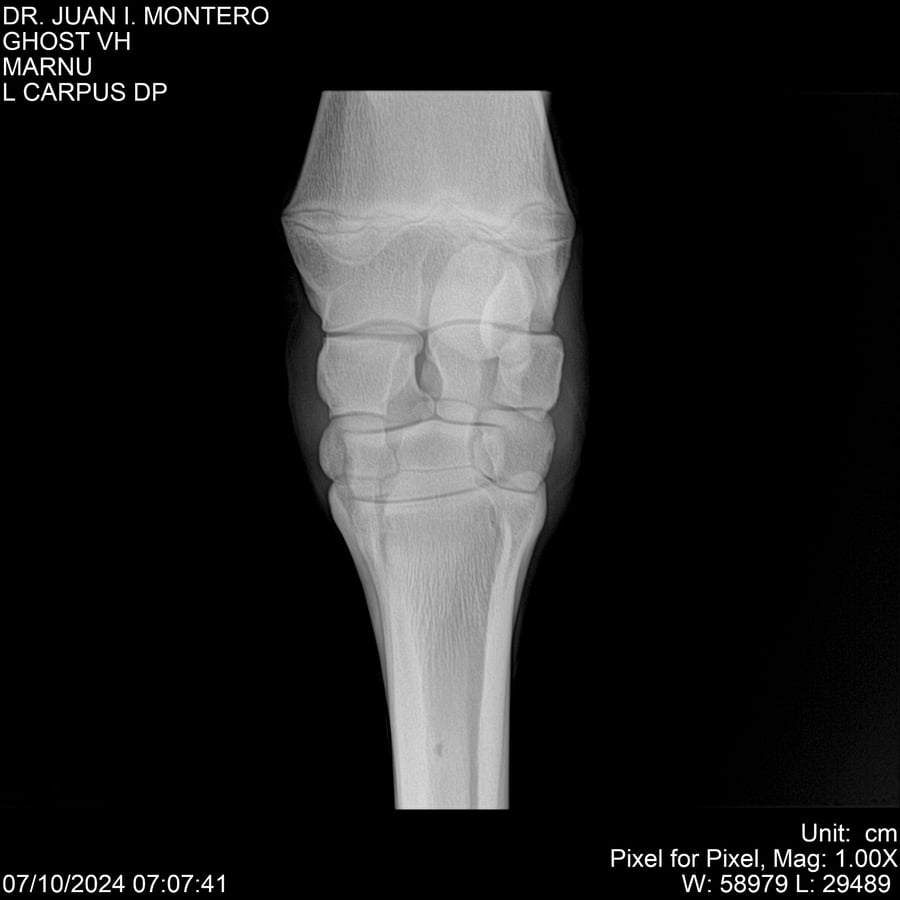

LOTE 15, GHOST VH 🔥 🔥 🔥 Lote Anterior Volver al remate Lote Siguiente Ficha Contacto Montevideo - Ficha del Lote Identificador: #282525 Categoría: Yeguarizos Montevideo - 69 Visualizaciones ClicData Contacto Empresa: Abelenda N. R., Walter Hugo Nombre*: Teléfono* : E-mail* : Mensaje Enviar Registrese gratis Este contenido Exclusivo está disponible sólo para usuarios registrados Ingresar